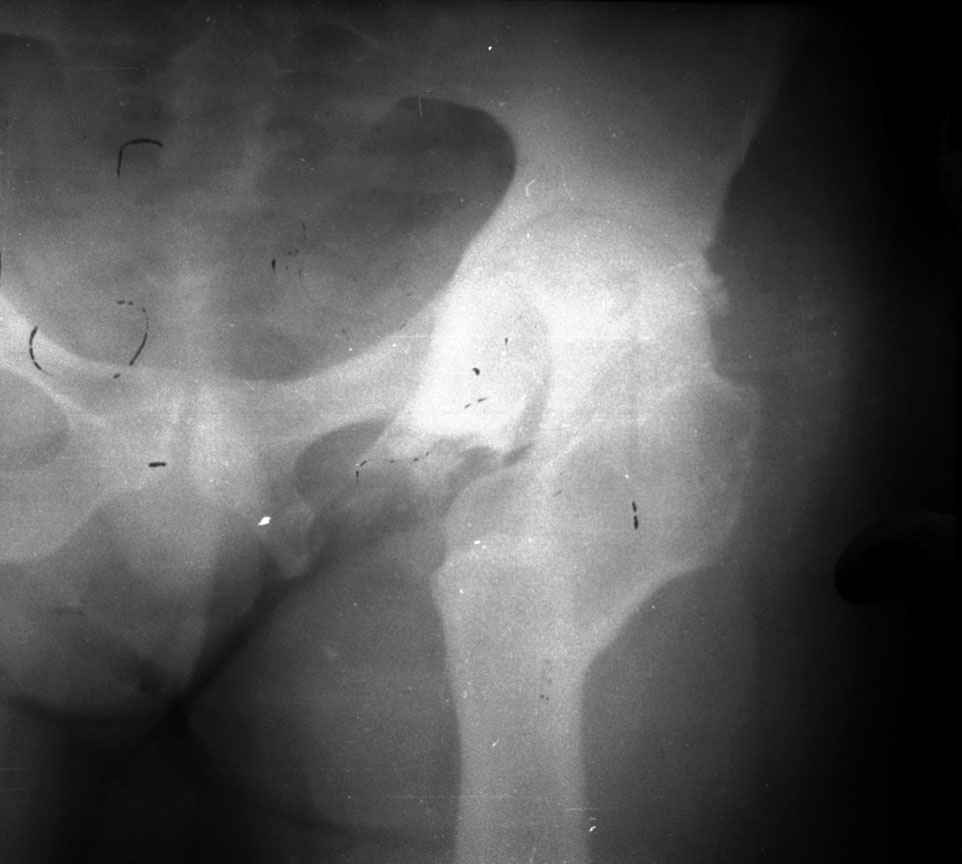

.........наверное не повезло. Но иногда это выход и очень хороший. М., 21 года спрыгнул в Армии с машины с исходом в гнойный коксит, свищевой формой в течении 1,5 лет. Операция проведена в 1988 году. результат хороший и сейчас и мы с пациентом хорошие приятели (Рентг-гр и фото прилагаю).